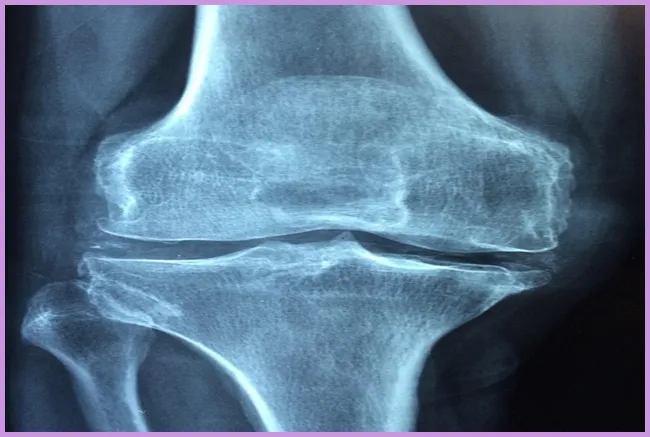

- 퇴행성 관절염: 나이가 들면서 관절의 연골이 마모되어 생기는 질환으로, 고관절 통증을 유발할 수 있습니다.